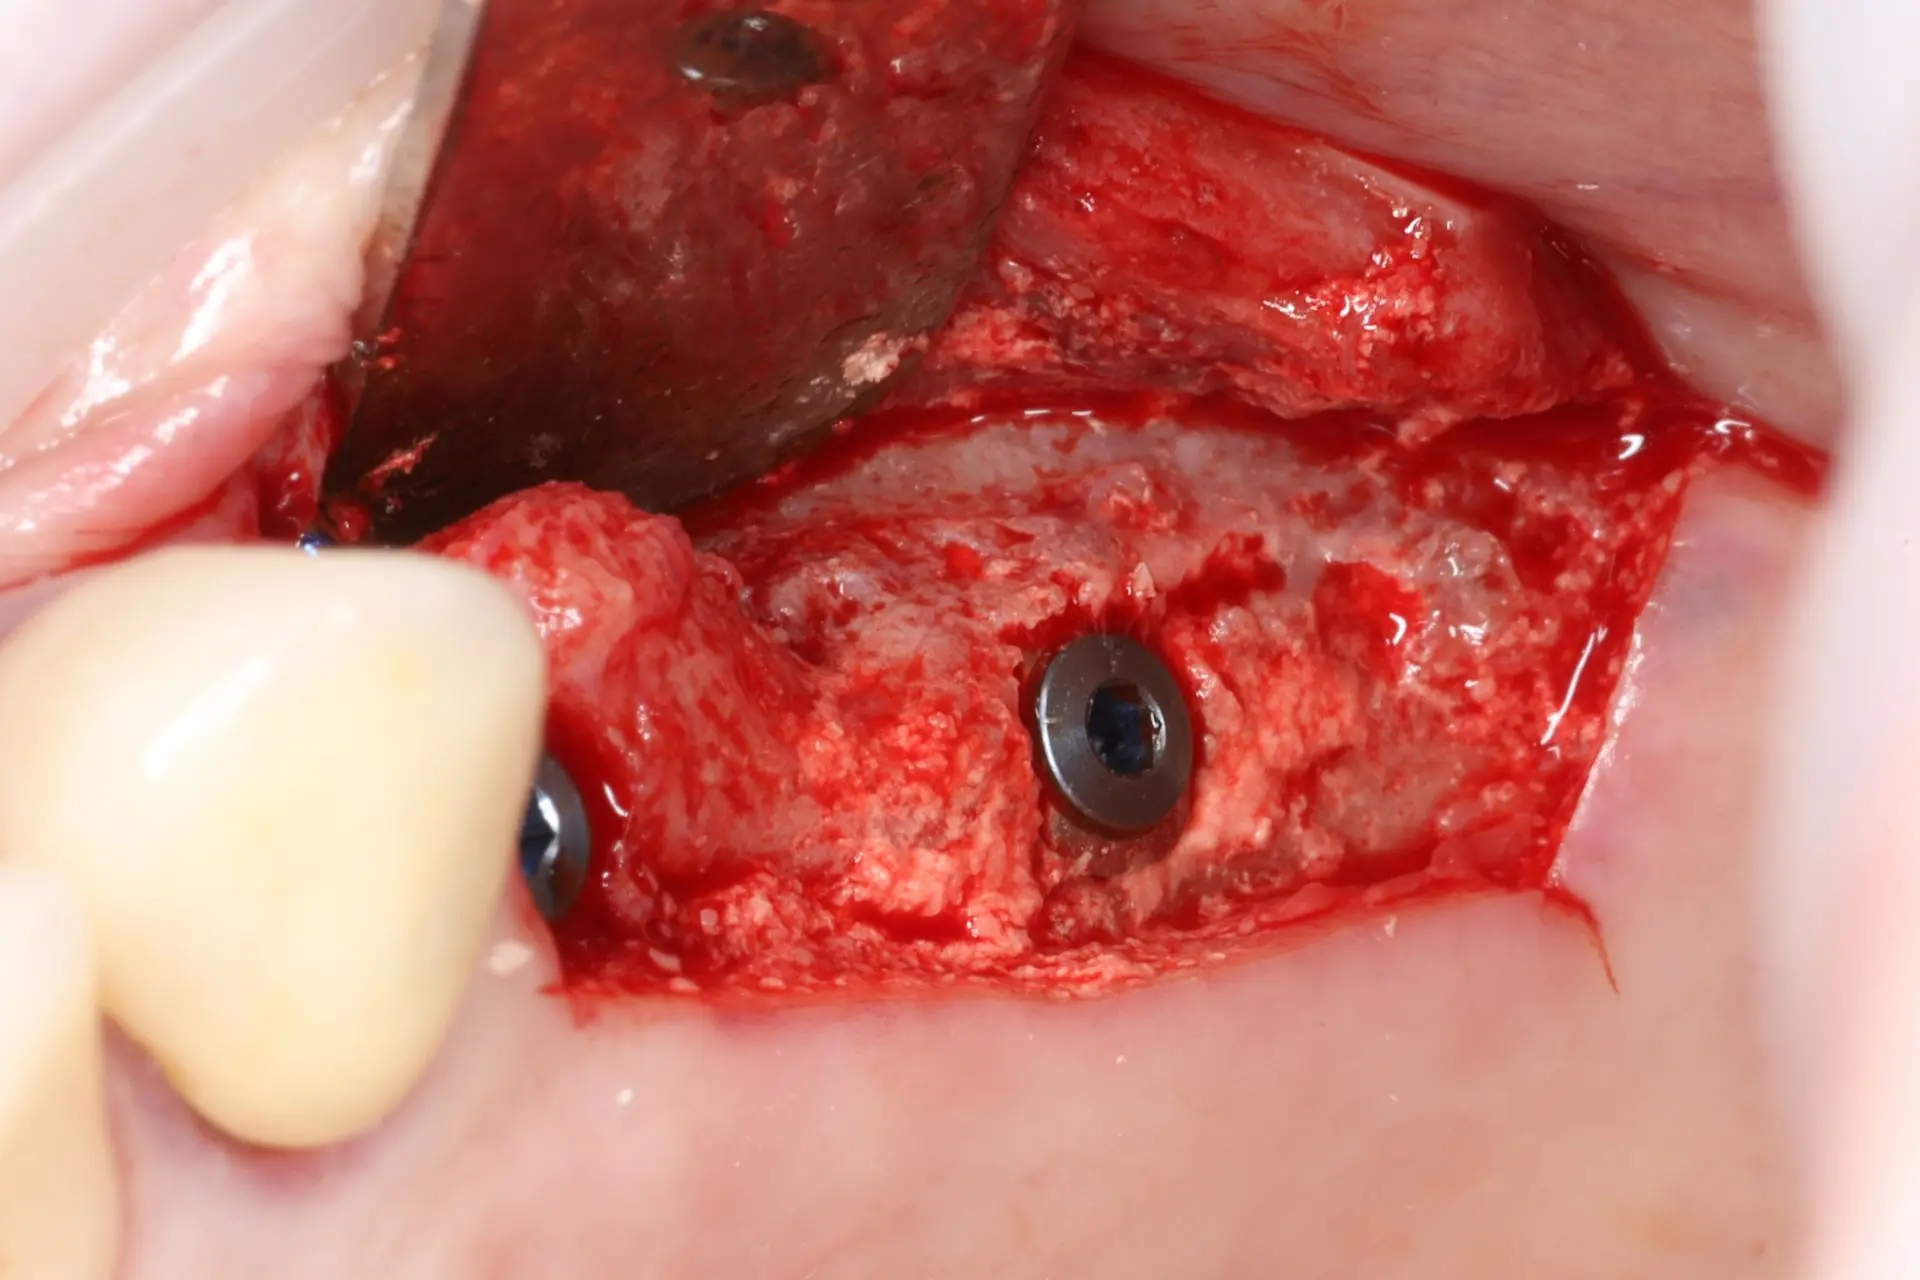

Seminaariesitykset keskittyvät täysin synteettiseen EthOss-biomateriaaliin, joka on kehitetty edistämään potilaan omaa luun uudistumista hammasimplanttien ja suukirurgian yhteydessä. EthOss koostuu β-trikalsiumfosfaatista ja kalsiumsulfaatista, jotka luovat ihanteelliset olosuhteet luun kasvulle ilman sulamattomia vieraspartikkeleita tai eläinperäisiä aineita, korvautuen kokonaan elävällä isäntäluulla noin 6–12 kuukaudessa.

Esityksissä käsitellään materiaalin valmistelua, käyttöä luusiirteissä sekä kliinisiä tuloksia, kuten nopeaa luunmuodostusta (jopa 50 % uutta luuta 12 viikossa), ilman tarvetta erilliselle kollageenikalvolle.

This lecture will explore how surgical simplicity combined with biologically active materials can achieve outstanding results across a range of indications — from socket preservation and regeneration to sinus lifting. Through clinical cases and practical protocols, Dr. Stuart Kilner will demonstrate how to optimise handling, improve efficiency, and achieve stable regeneration by working with, not against, the body’s innate capacity to heal.

EHL suu- ja leukakirurgi Ilkka Pallosella on jo yli viiden vuoden kokemus EthOss-luudutusmateriaalin käytöstä potilastyössään. Esityksessä käydään läpi eri käyttöindikaatioita, materiaalin käyttöönottoa sekä yleisiä käytännön neuvoja niin aloittelijallekin, kuin myös kokeneemmallekin kliinikolle.

EthOss cases by Dr Ilkka Pallonen